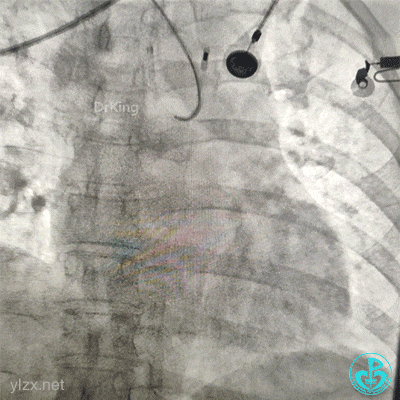

2.0×15mm球囊预扩张后。

植入4.0×13mm支架1枚。

交换导丝后扩支架网眼。